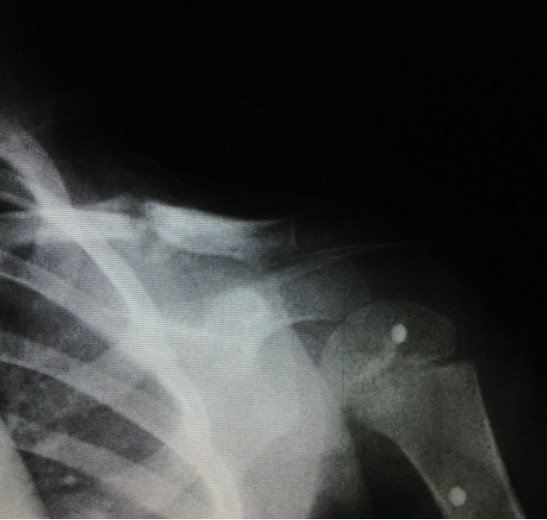

宝宝3岁半出车祸左锁骨骨折

2012.10.7日发送车祸,X片确诊为左锁骨骨折。现在已经自行把八字绷带取下,请问这样做可以吗?因为孩子的腋下已经开始有轻微溃烂的症状(掉干壳壳)前段时间因为出车祸导致孩子的左锁骨骨折,去医院打了八字绷带,刚好一个月去医院复查,医生说已经开始长骨痂,建议继续八字绷带半个月,今天宝宝一直吵着说腋下痛,我才发现宝宝的腋下有那种干裂的壳状的掉出,而且腋下非常的红。孩子的奶奶处于心痛孩子,就把绷带给取了,请问这样做妥当吗?会影响孩子骨折的生长吗?如可以取下,家长应该注意些什么细节呢?谢谢!“下面的X光片拍摄于2012年11月3日”